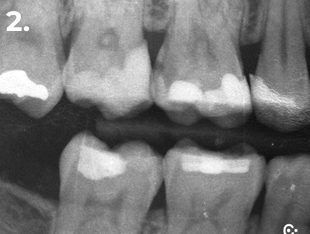

Fig. 2 Radiografía de aleta de mordida Inicial

Paciente que acude a consulta refiriendo molestias en la zona del primer cuadrante. La exploración clínica y radiográfica reveló la presencia de una caries profunda distal, estableciéndose el diagnóstico pulpar de pulpitis reversible. Con el objetivo de lograr un adecuado punto de contacto tanto mesial como distal, se procedió a la eliminación completa de la restauración existente. El procedimiento se realizó bajo aislamiento absoluto, utilizando para el encofrado el sistema de matrices seccionales HALO. En la imagen clínica y radiográfica final se observan perfiles de emergencia bien conformados, convexos, así como puntos de contacto adecuados.